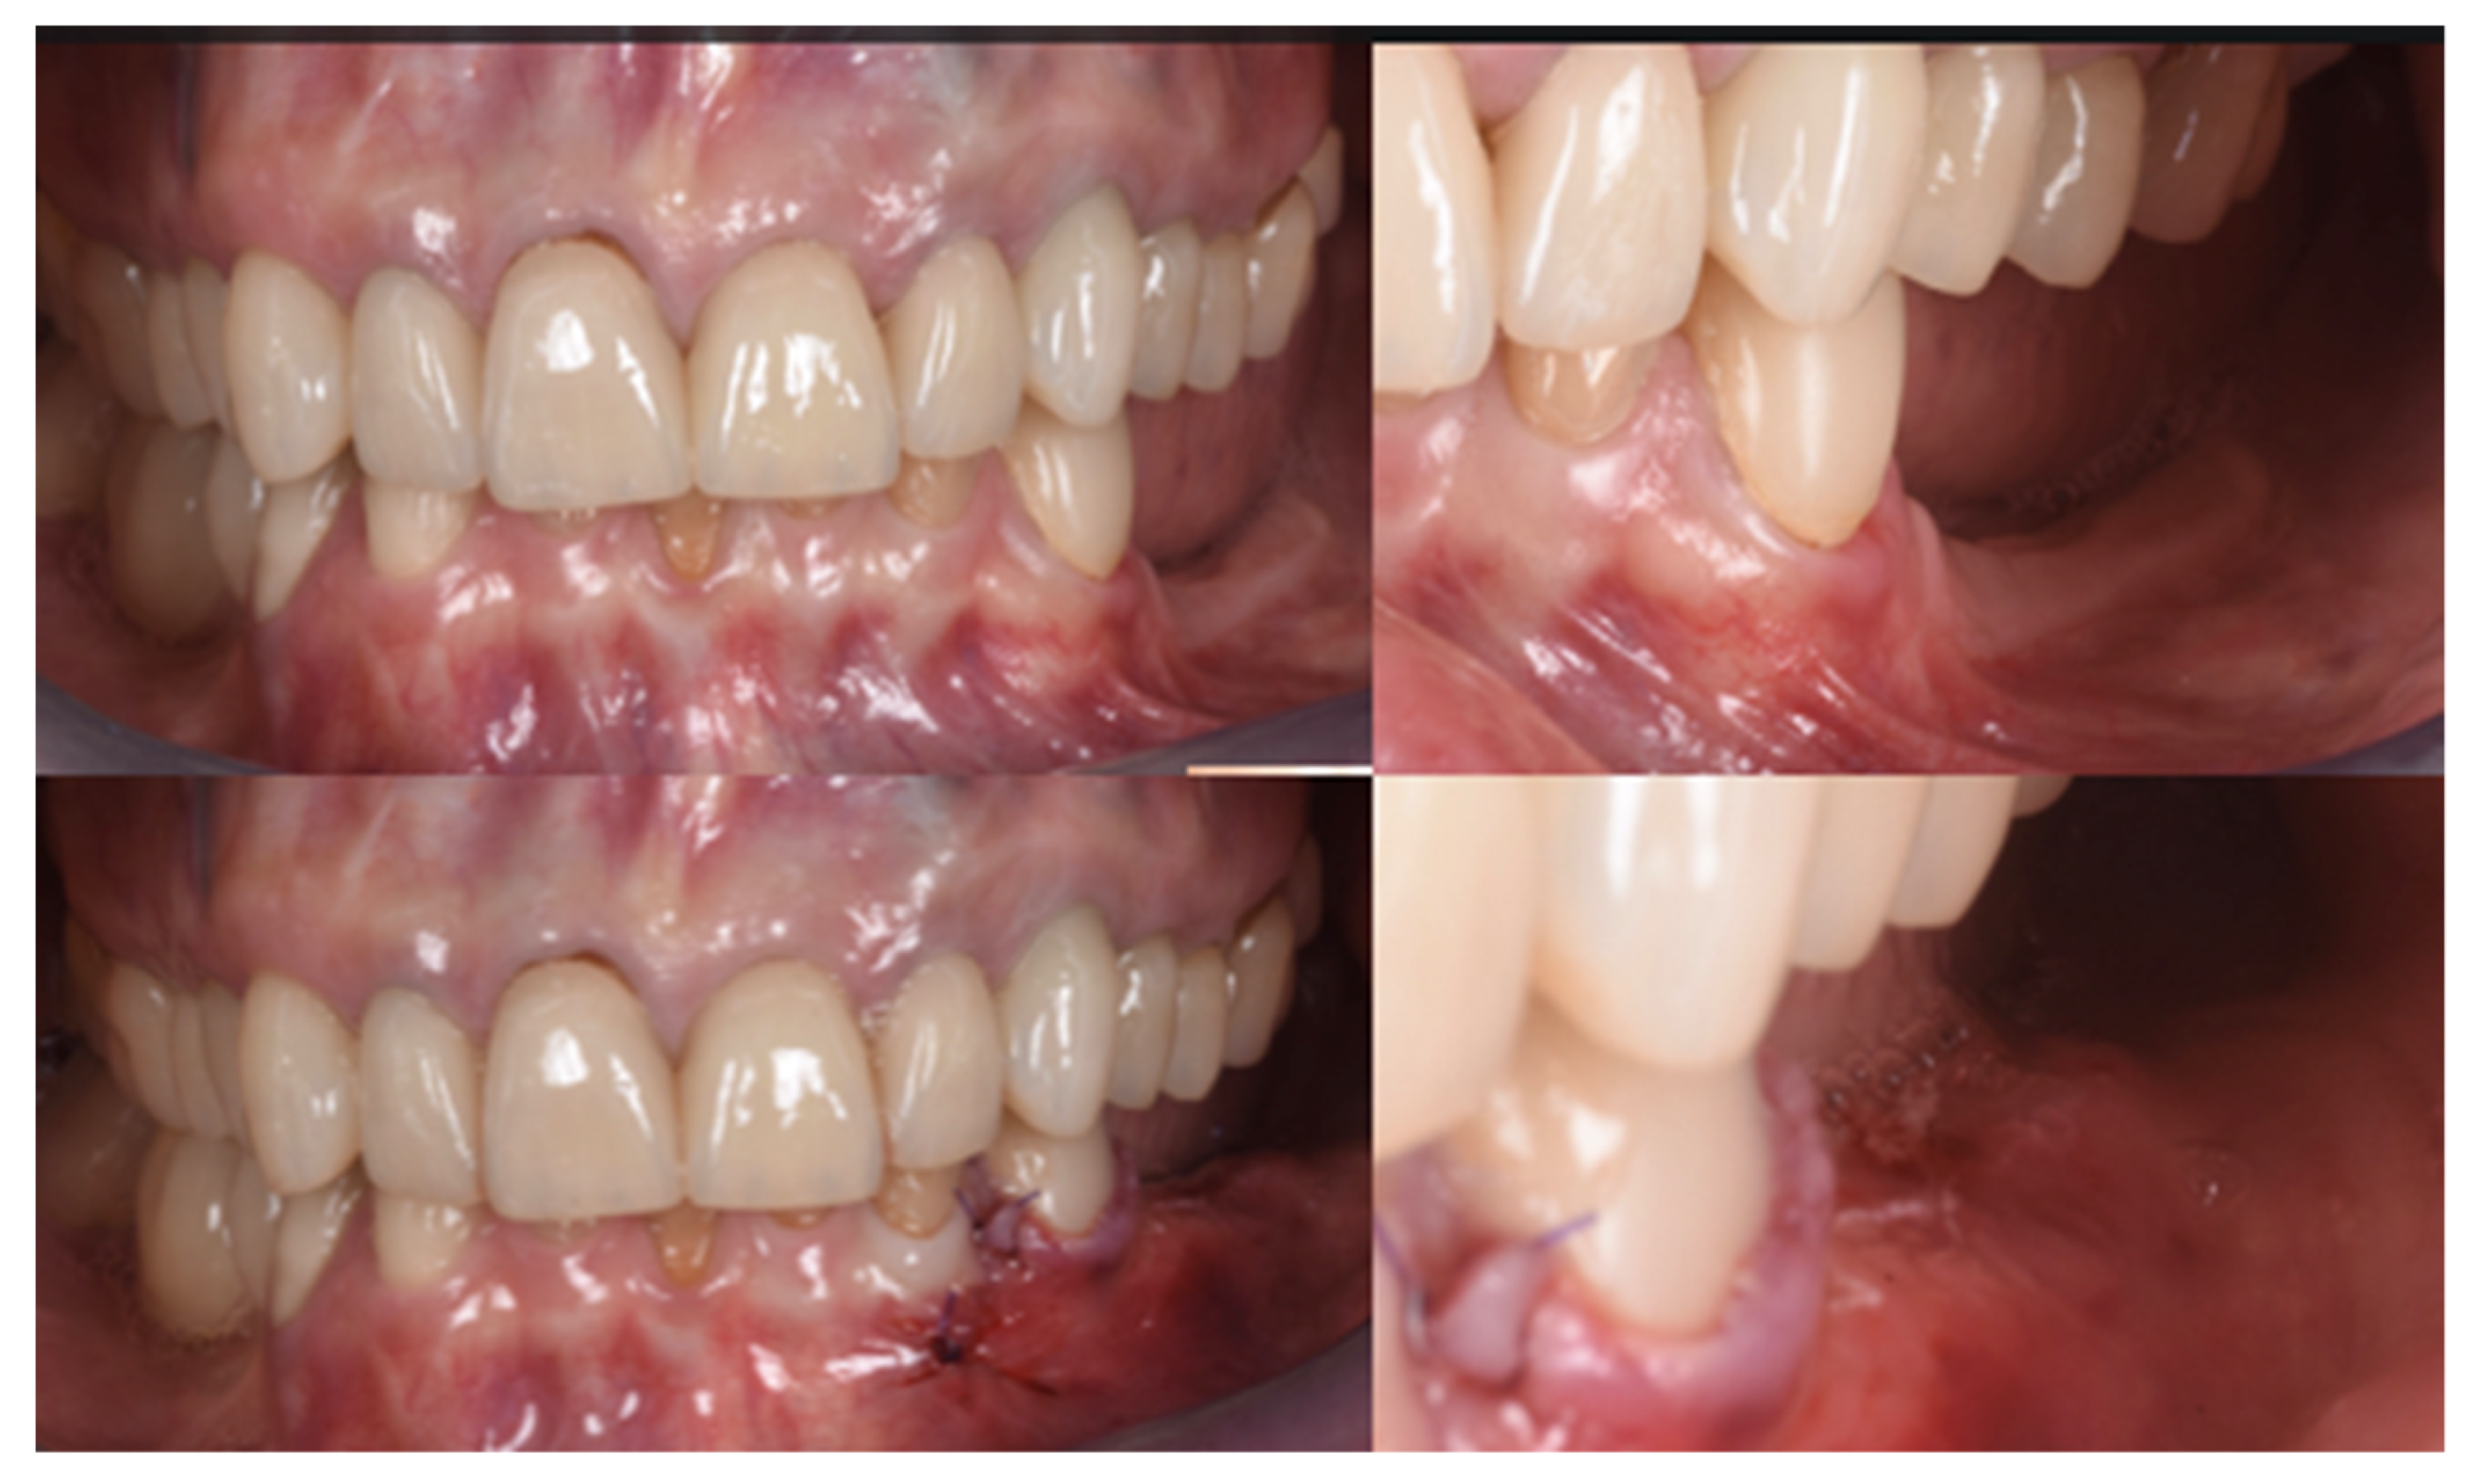

3.2. Soft Tissue Augmentation

| T1 | Mucogingival Surgery (0 months) | Free gingival graft |